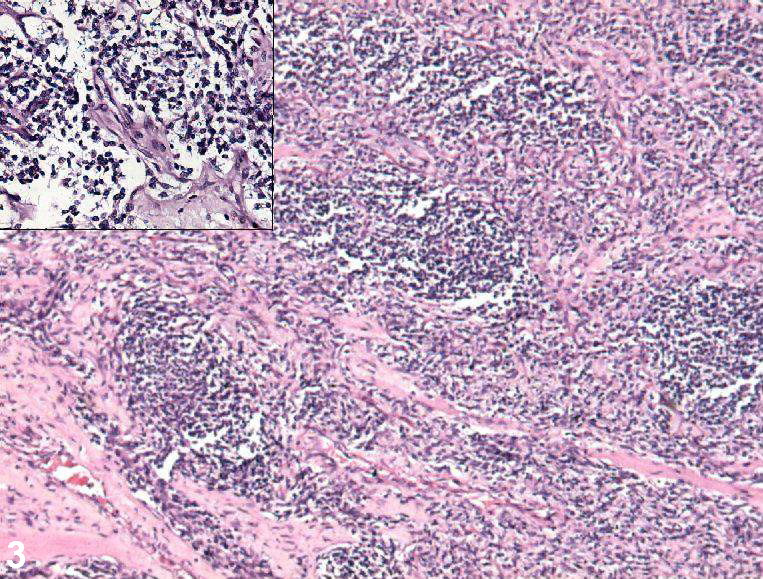

횡문근육종은 다른 암과의 유사성과 분화 수준의 다양성으로 인해 진단이 어렵다. H&E 염색에서의 소견을 통해 소청색원형세포종양으로 분류되기도 한다. 소청색원형세포종양을 보이는 다른 종류의 암에는 신경모세포종, 유잉육종, 림프종 등이 있으며, 횡문근육종을 진단할 때는 이와 유사한 소견을 보이는 질병들을 명확하게 배제해야 한다.[81]

횡문근육종의 결정적인 진단적 특징은 현미경하에서 근육 형성(통통하고 분홍색 세포질로 나타남)을 동반한 악성 골격근 분화를 확인하는 것이다.[4] 가로 줄무늬가 있을 수도 있고 없을 수도 있다. 정확한 진단은 일반적으로 미오제닌, 근육 특이적 액틴, 데스민, D-미오신, myoD1과 같은 근육 특이적 단백질에 대한 면역조직화학 염색을 통해 이루어진다.[33][37][34] 특히 미오제닌은 횡문근육종에 매우 특이적인 것으로 나타났지만,[35] 각 단백질 표지자의 진단적 중요성은 악성 세포의 유형과 위치에 따라 다를 수 있다. 폐포형 횡문근육종은 근육 특이적 단백질 염색이 더 강한 경향이 있다. 전자 현미경 또한 진단에 도움이 될 수 있으며, 액틴과 미오신 또는 Z 띠의 존재는 횡문근육종의 양성 진단을 나타낸다.[4][37]